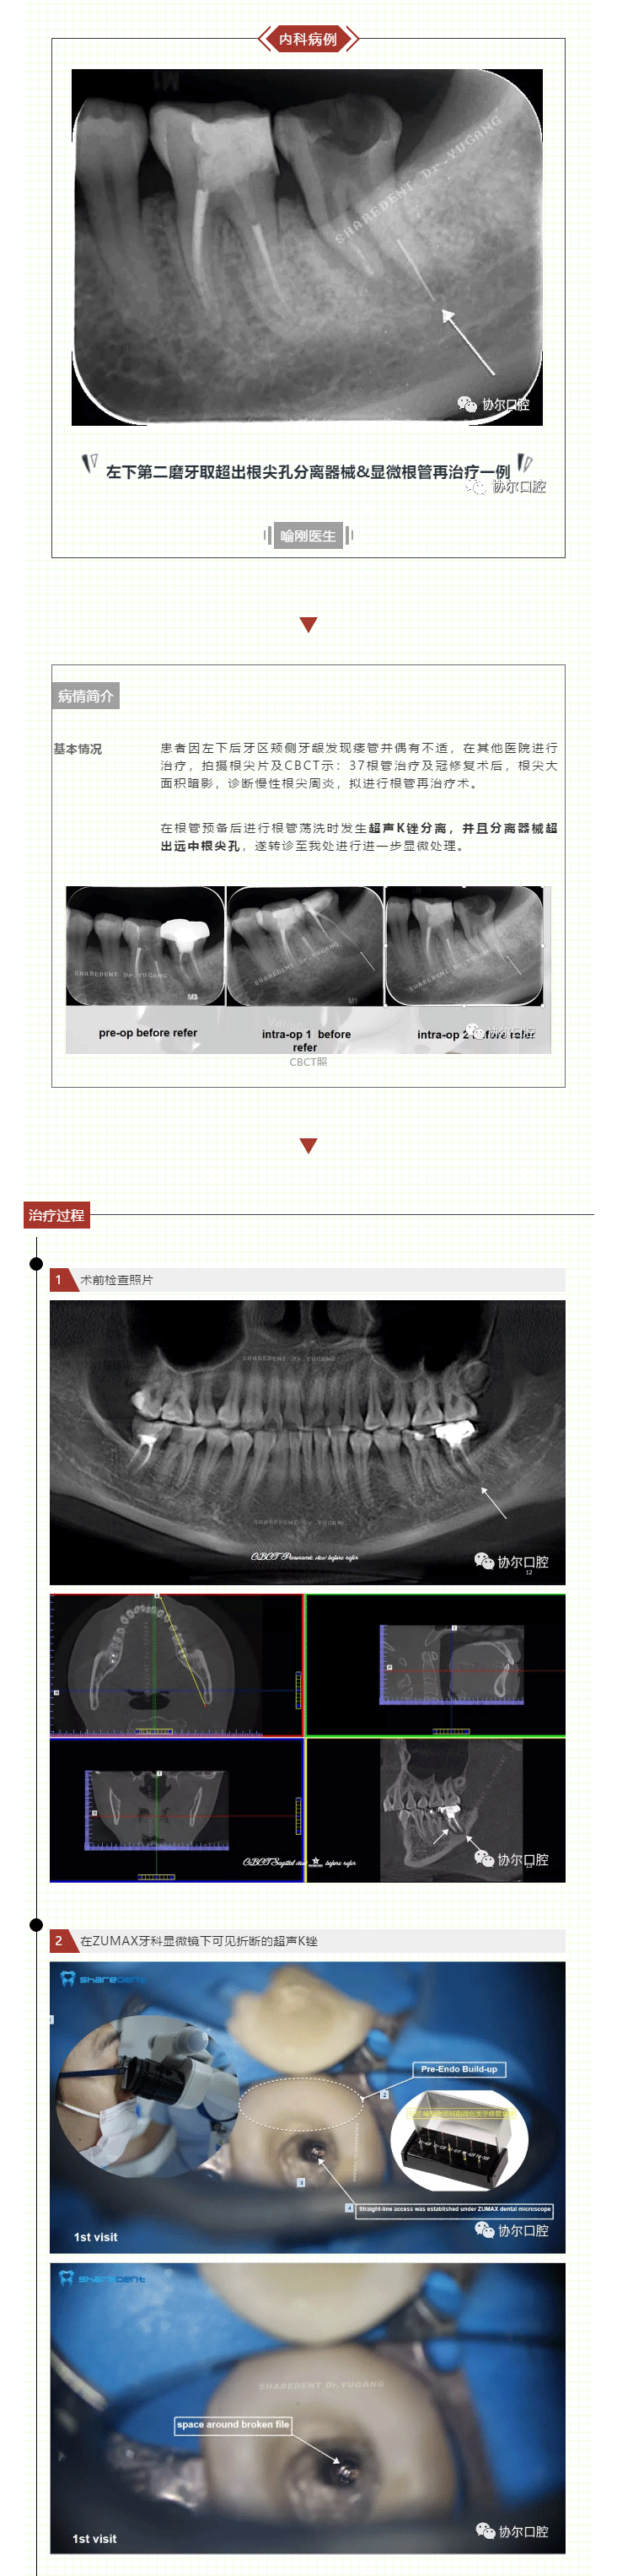

协尔周秀咫尺之间,根管妙手,患牙重生